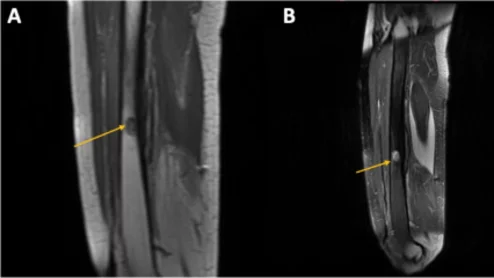

osseous lesion on MRI.

Radiation-induced osteitis may not cause clinical symptoms, but its presence often sparks concerns about malignancy.